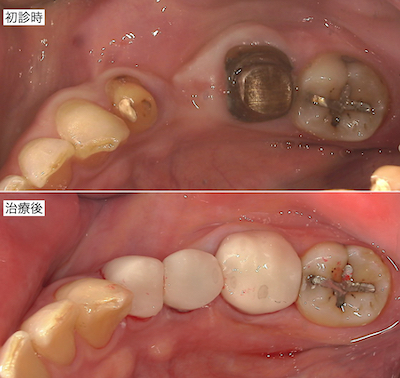

治療前後の比較です。